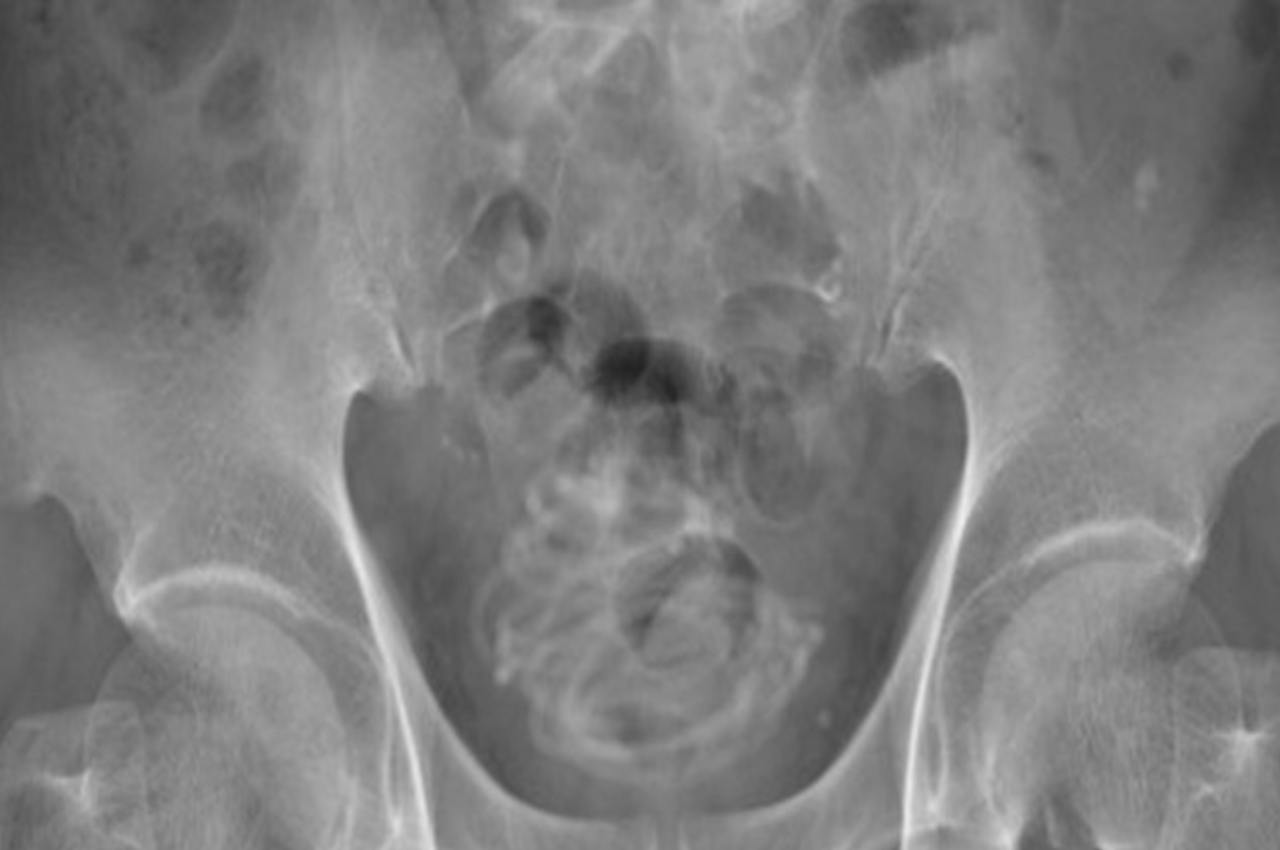

Homem enfia corda de pular de 2,3 metros no pênis e surpreende médicos

Através de um raio-x, os médicos constataram que o objeto foi parar na bexiga do paciente de 79 anos.